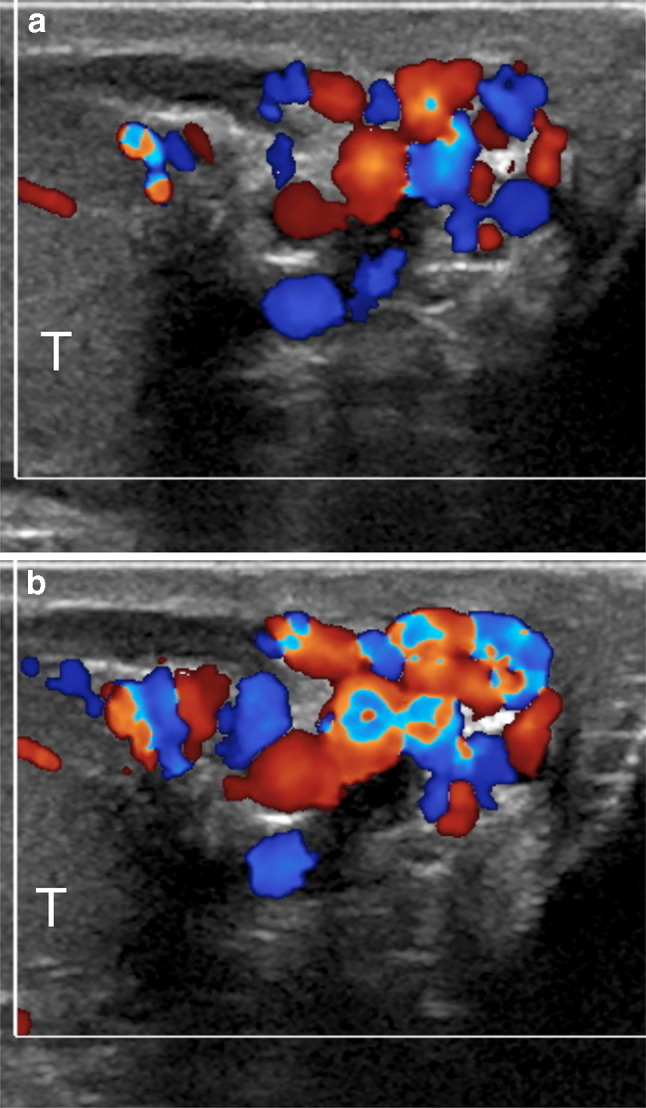

One of the problems encountered when comparing different US studies for varicoceles concerns the variability of reporting. A standard report should be useful, in which all the relevant data are collected. The variable clinical practice in reporting patients with varicoceles reflects the differences in examination techniques. The ESUR-SPIWG recommends describing the examination technique and reporting all the US parameters used to evaluate the patient. It also suggests grading varicoceles according to the Sarteschi’s classification (Figs. 3, 4, 5, 6, Table 2, recommendations 12–13).

Fig.5.

Sarteschi’s grade III varicocele. Colour Doppler images obtained at rest (a) and during Valsalva (b) showing dilated veins to the inferior pole of the testis (T) with reflux during Valsalva

Fig.6.

Sarteschi’s grade IV varicocele. Colour Doppler images obtained in supine position at rest (a) and while standing during Valsalva (b). Dilated veins with reflux are visible also at rest. Reflux increases while standing during Valsalva (T = testis)